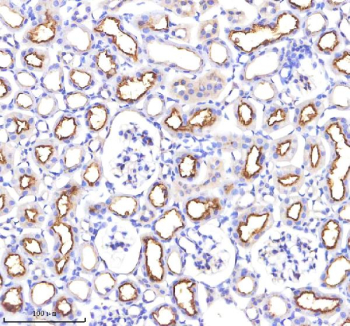

Immunohistochemical staining of ACE using anti-ACE antibody. ACE was detected in a paraffin-embedded section of mouse kidney tissue. Heat mediated antigen retrieval was performed in EDTA buffer (pH 8.0, epitope retrieval solution). The tissue section was blocked with 10% goat serum. The tissue section was then incubated with 2 ug/ml rabbit anti-ACE antibody overnight at 4oC. Peroxidase Conjugated Goat Anti-rabbit IgG was used as secondary antibody and incubated for 30 minutes at 37oC. The tissue section was developed using an HRP secondary and DAB substrate.